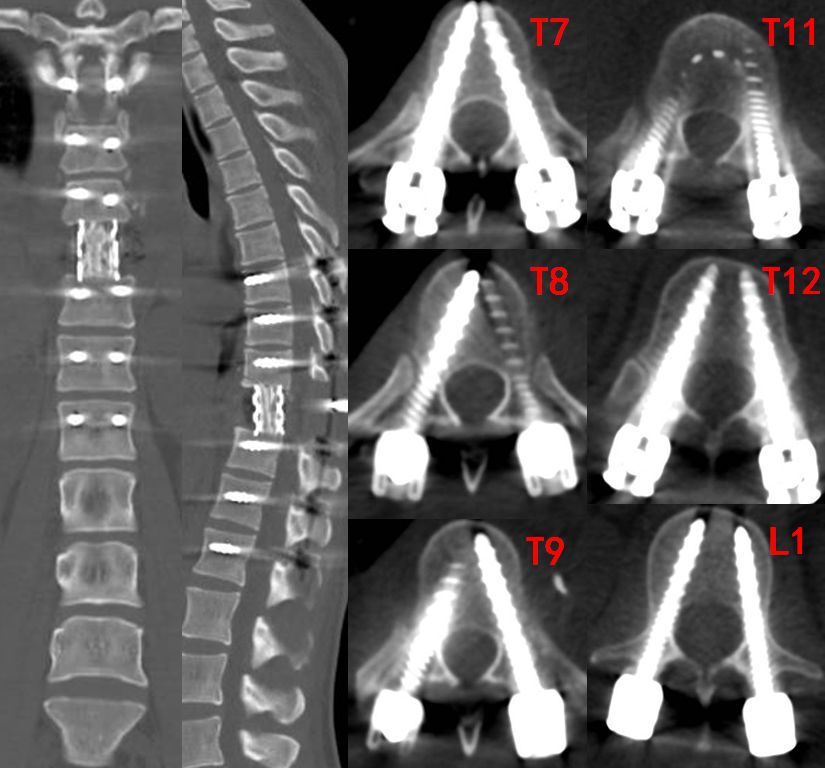

术后复查CT显示,内固定位置满意,脊柱稳定性得到重建